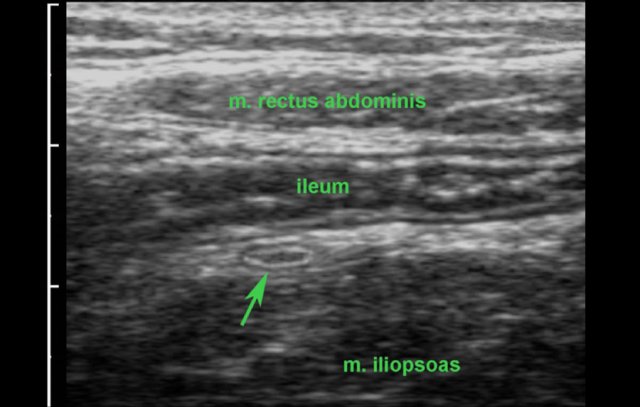

In this lean person, the normal terminal ileum and the normal, compressed appendix (arrow) are visualized on a tablet connected to a 1200 euro probe.